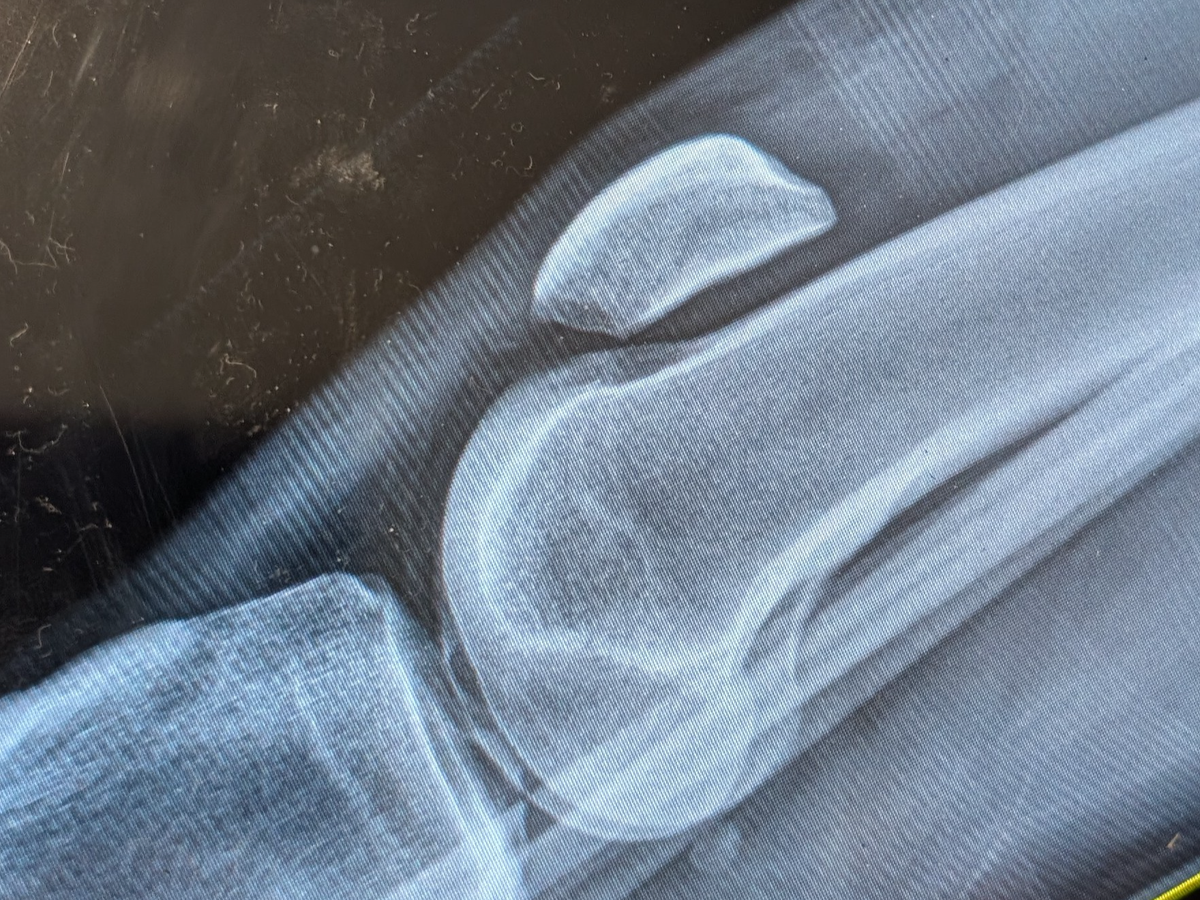

I took a bad fall off a ladder doing some home improvements at my house. I completely tore my patellar tendon, leaving my kneecap floating at thigh level.